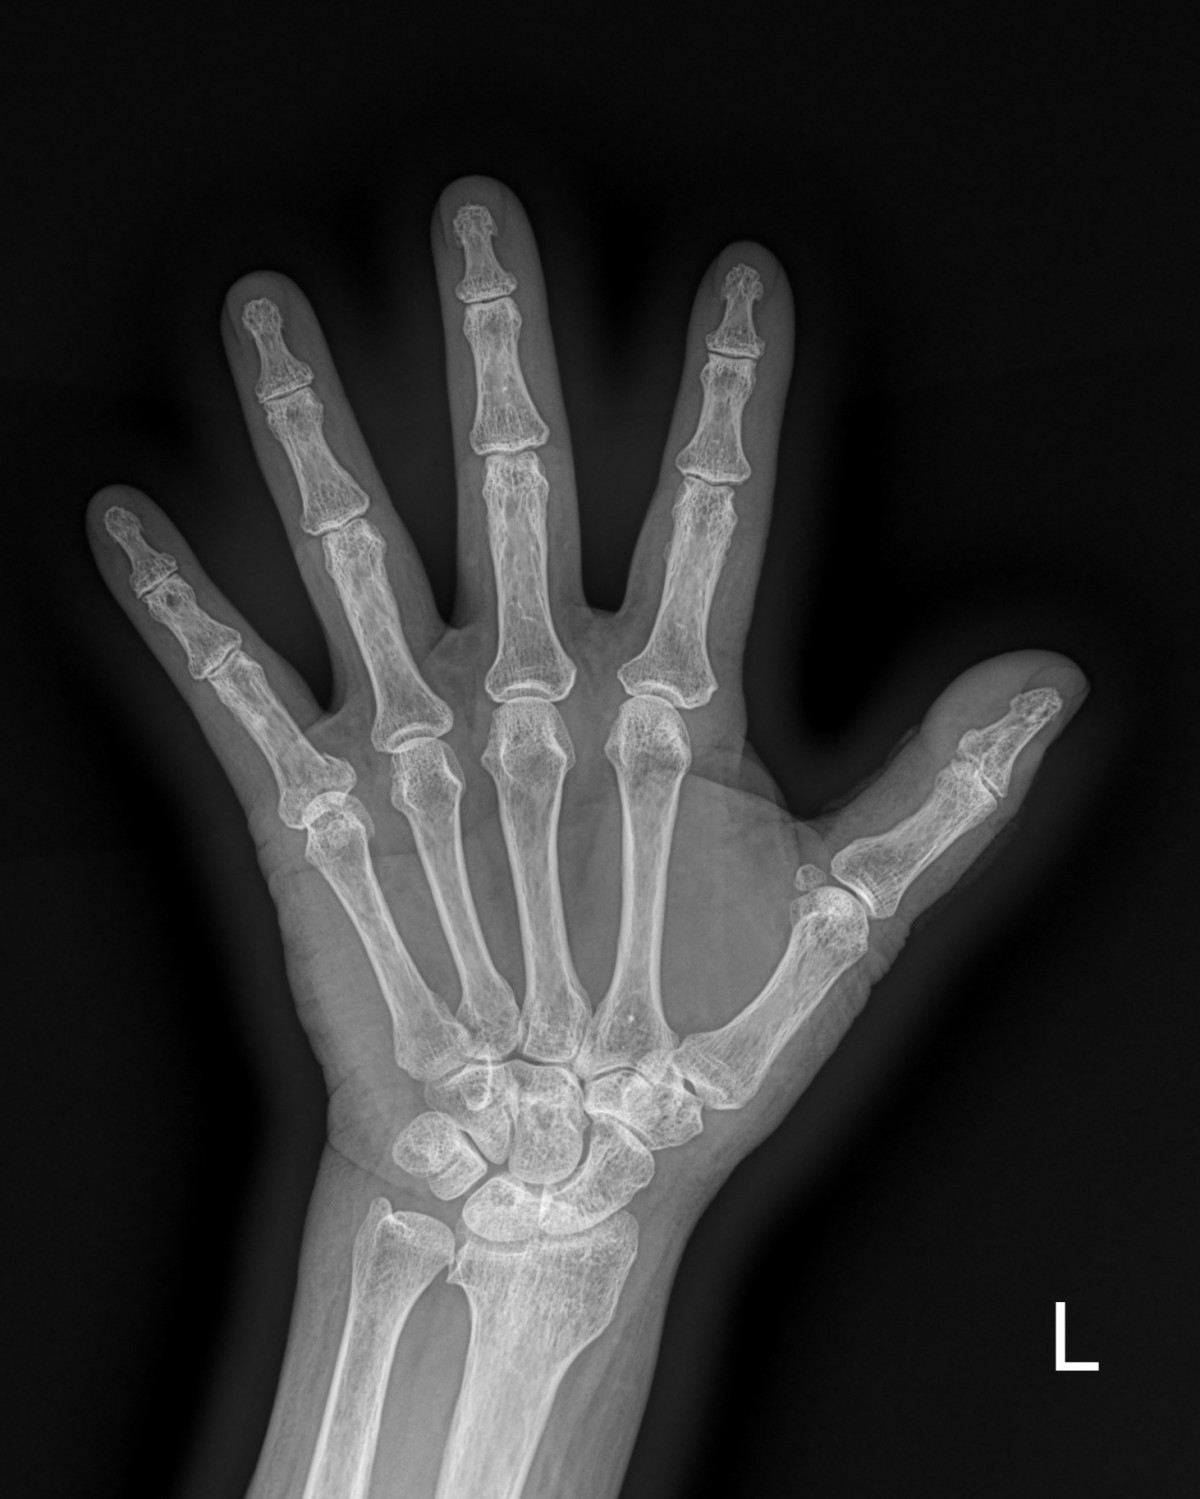

이재상원장님 손가락 골절 수술 안언O 환자

dae765e4d9ac96aee867c9d6292d8784_1758003476_6816.jpg